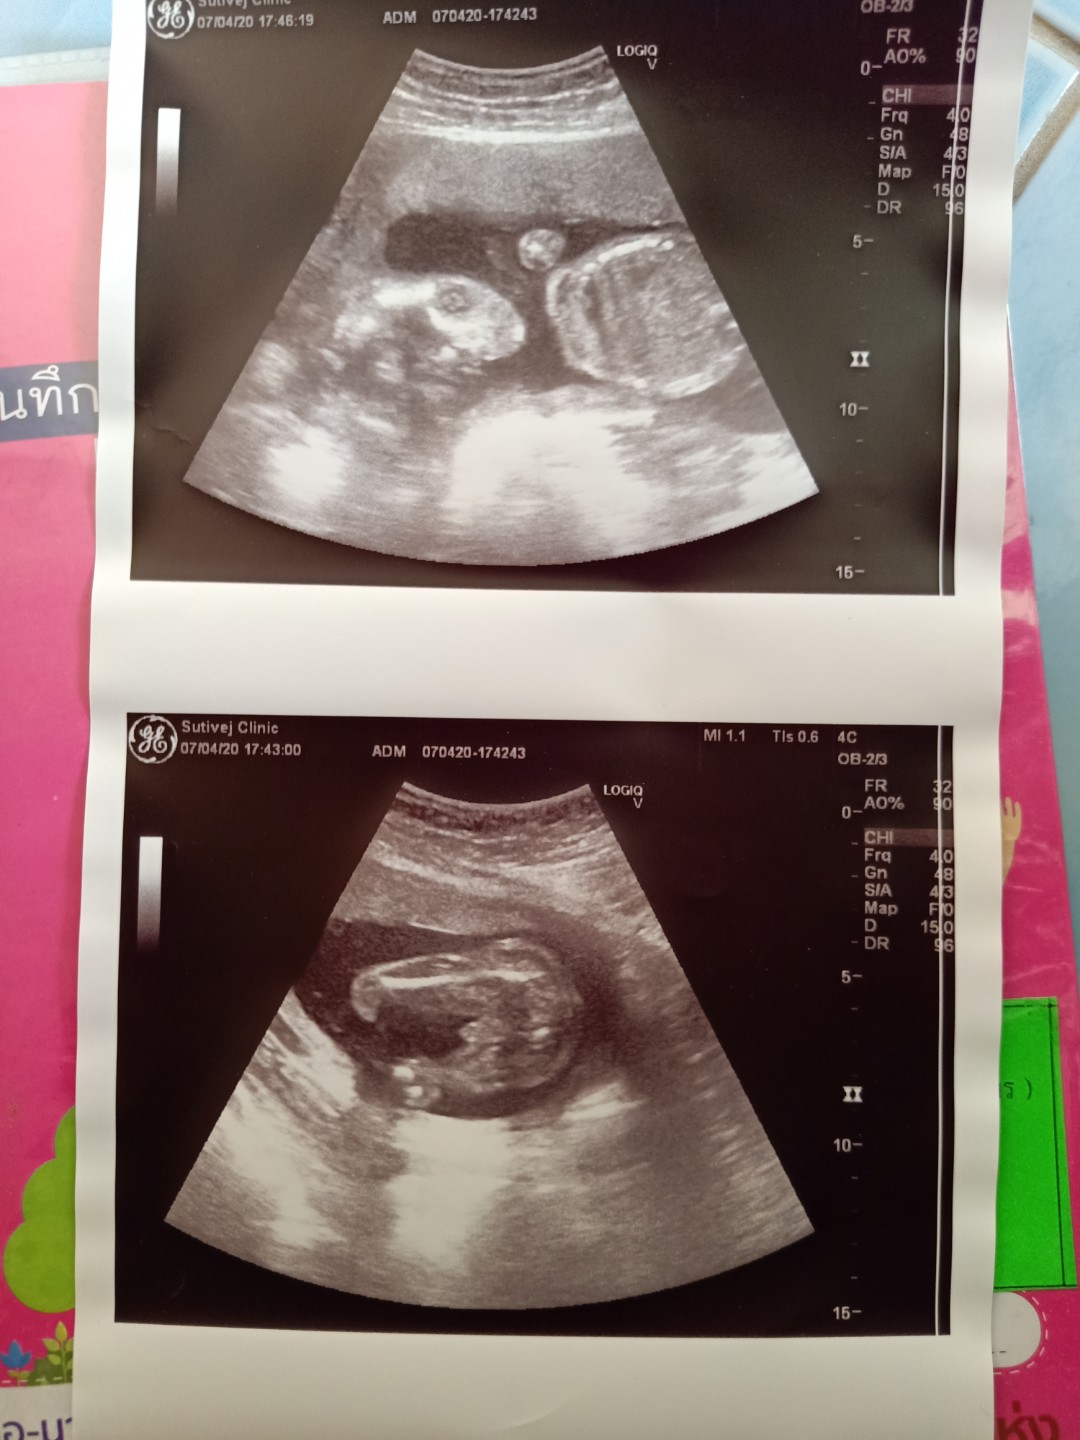

ดีใจมากค้า ได้ลูกชายสมใจ. ขอดูรูปซาวแม่ทีมกันยาหน่อยค้าาาา ได้ลูกชายรึลูกสาวกันน้อ บ้านนี้คนแรกได้ลูกสาวแล้วคนสองหมอบอกลูกชาย ดีใจม้ากกกกกกก